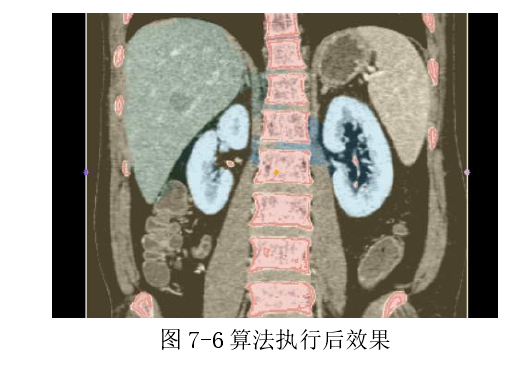

5.视图绘图工具

6.2.3 图像描绘与区域生长

如下图首先在图 7-5 左图中选择相应的描绘工具然后在切片视图中选取不同器官组织先标记为不同的颜色,之后就是选择相应的颜色后在图中标记种子点,为了分割出完整器官模型,需要选择一个颜色标记为对照区域(图中黄色部分),最后进行区域生长后产生效果如图(7-6)。如果出现了过生长或空洞的效果,则在分割基础上再选取一些种子点即可。